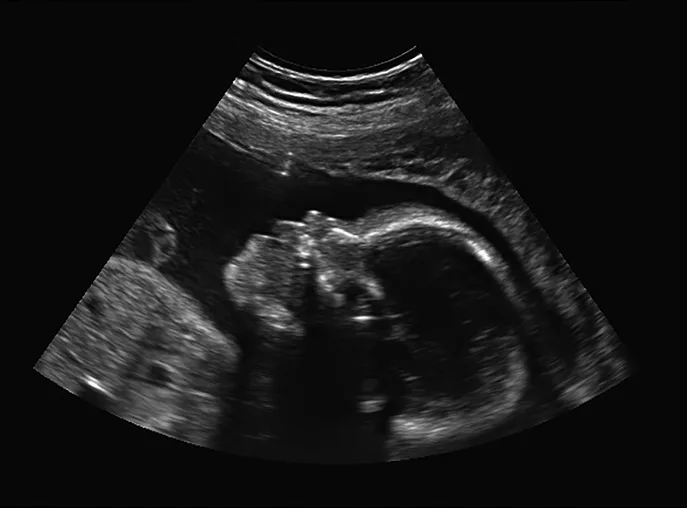

Ultrasound self-examination of the fetus by pregnant veterinary professionals is a growing trend in veterinary medicine. Is this a harmless action, or could there be an unforeseen downside? Let’s take a look at some of the issues.

In human medicine, the number of scans performed during pregnancy varies according to physician preference and patient needs. Scans are used to provide information about fetal health, to determine gender, and to obtain printed images of the fetus or fetuses for expectant parents; ultrasound visualization of the pregnancy can also facilitate an emotional connection to the fetus. All of these objectives are important.

• Enjoying the novelty of seeing the fetus develop over time or the need to have more keepsake images or videos.

Duration of the probe use also influences how much acoustic energy is delivered to the fetus. Long scan times or fixed probe positions that linger can deliver more acoustic energy per volume of tissue and therefore are less desirable than well-planned methodical examination by a professional sonographer.2,5 With ultrasound self-examinations, the user may not be familiar with operation protocols (eg, adjusting parameters that would affect TI and MI levels) or may not realize that efficient use of the probe can be key in minimizing fetal exposure.